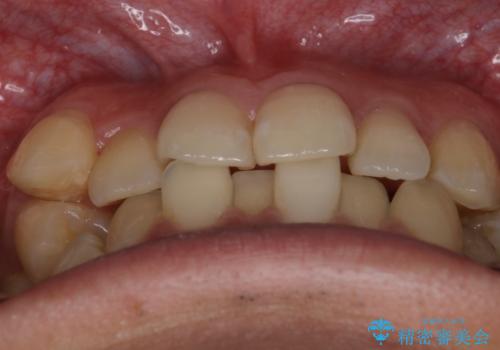

- 上の八重歯と下の歯のがたつきを主訴に来院されました。

気にされていた八重歯とがたつきが綺麗に改善されました。